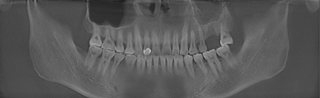

郑先生口腔内部全景片

种牙成功后的郑先生口腔ct全景